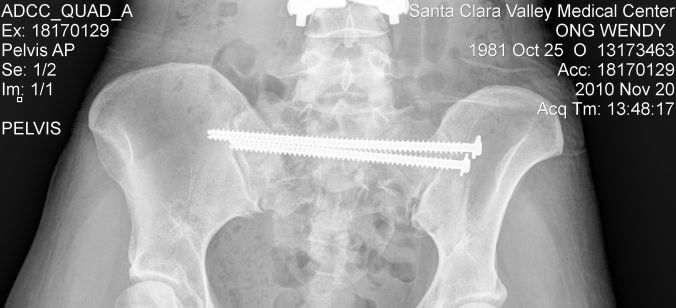

Aside from the vertebral fractures and Spinal Cord damage, my L2 vertebra exploded upon impact, my pelvis broke in multiple places and my sacrum was reduced to a collection of pebbles. The process of piecing back together humpty-dumpty was a long, arduous and very painful one.

You can see I am fused between T12 and L4, with a cage in place of my L2 verebra. I am also fused between T6-T8.